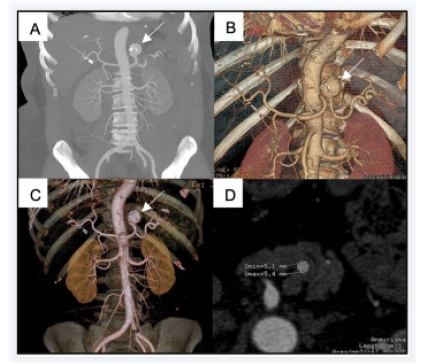

Complete exclusion of the aneurysm and patency of the splenic artery were confirmed at 6 months CT follow-up imaging (Figure 3). The patient became completely asymptomatic at follow-up.

Figure 3: CT angiography at 6-month follow-up: MIP (A) and 3D (B, C) reconstructions show complete exclusion of the aneurysm, patency of the splenic artery, and correct location of stent-grafts. Axial CT image (D) evidence normal splenic parenchyma in the venous phase, without signs of complications.